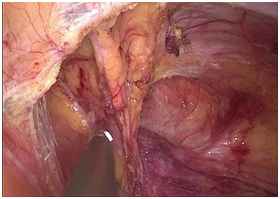

手术图片

腹腔镜腹股沟疝修补术(TAPP)